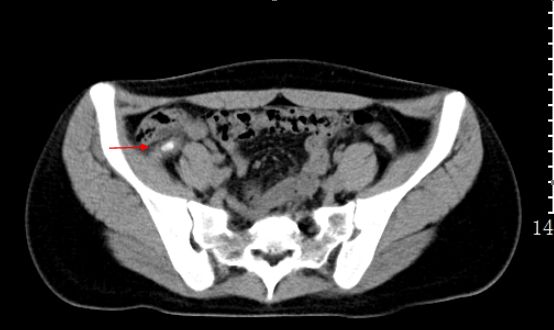

3)急性阑尾炎:是外科常见病,居各种急腹症的首位。其临床表现为转移性右下腹痛、恶心、呕吐,多数病人白细胞和中性粒细胞计数增高。右下腹阑尾区(麦氏点)压痛、反跳痛,是该病重要体征。

CT是其最具价值的影像检查手段。急性阑尾炎主要表现为阑尾增粗肿大,壁增厚,腔内积液积气和粪石,阑尾周围脂肪密度增高,少量积液,腹膜增厚。如出现肠腔外气体、肠腔外粪石及增强扫描阑尾壁缺损需诊断穿孔。

急性阑尾炎:CT平扫,阑尾增粗肿胀,腔内可见高密度粪石,阑尾浆膜面模糊,周围少许渗出。